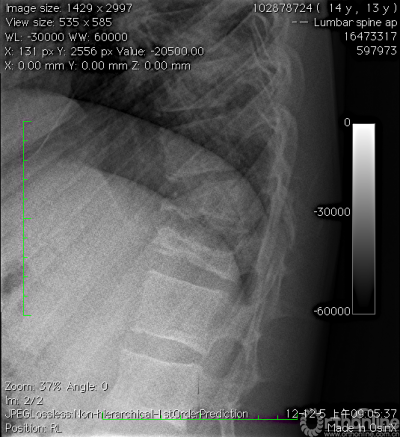

图4 患儿女,9岁,背部疼痛不适,术前胸椎侧位片,T8和T9椎体嗜酸性肉芽肿病变,椎体严重压缩变形。T8椎体上终板前缘骨骺破坏。